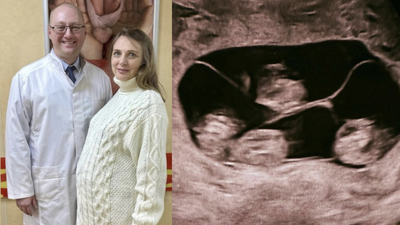

A rare and medically significant birth has been reported in St Petersburg, where a woman delivered four identical baby girls, marking the first such case officially recorded in Russia.The delivery, which took place at a maternity hospital in the city, has drawn attention due to its extreme rarity. Medical estimates suggest that monochorionic, or identical, quadruplets occur in around one in 15.5 million births. Globally, only about 15 such cases have been documented.All four babies were born at 32 weeks of pregnancy and are reported to be in stable condition. Their birth weights ranged between 1,360g and 1,640g, and their lengths were between 37cm and 41cm. Doctors described these figures as strong for babies born at this stage.In a statement shared by the hospital on Russia’s social media platform VKontakte, the team said, “Four charming sisters were born at 32 weeks. According to estimates, monochorionic (identical) quadruplets occur once in 15.5 million births. Such unique births have not been reported in the country.”What makes the case particularly complex is that all four babies developed from a single fertilised egg and shared one placenta, a condition known as a monochorionic pregnancy. In most multiple pregnancies, each baby has a separate placenta. Doctors note that such cases carry higher risks and require continuous monitoring.The hospital added, “For a 32-week pregnancy, this is an excellent result, made possible by the mother’s proper management in the antenatal department and the expertise of the doctors.”The delivery required the coordinated effort of a large medical team, including obstetricians, anaesthesiologists, intensive care specialists, midwives, and neonatal experts. Each baby was immediately attended to by neonatologists and specialised nurses to ensure proper care from the first moments after birth.According to the hospital, the procedure was led by chief physician Professor Anton Mikhailov, along with a team of specialists from the prenatal department and obstetrics unit. The operation was described as highly complex, requiring precision and teamwork throughout.Doctors explained that identical, or monozygotic, pregnancies occur when a single fertilised egg splits into multiple embryos, resulting in babies with identical genetic makeup and the same sex. There is no known way to predict or prevent such occurrences.The case is now being seen as a milestone in Russian medical practice, highlighting both the rarity of the event and the level of care required to manage such a high-risk pregnancy successfully.